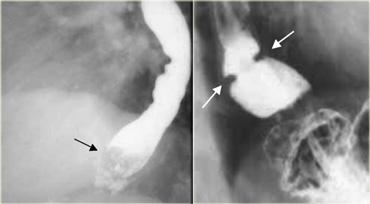

Hình bên trái là một bệnh nhân thực quản Barrett.

Hình ảnh niêm mạc dạng lưới là đặc trưng của dị sản trụ Barrett, đặc biệt khi kết hợp với hẹp dạng màng (mũi tên).

Hình bên trái là một bệnh nhân thực quản Barrett có ung thư biểu mô tuyến.

Có các nếp niêm mạc đoạn xa bất thường.

Bờ trên của ung thư biểu mô tuyến tạo góc vuông với thành thực quản (mũi tên), gợi ý tổn thương thành thực quản ở bệnh nhân GERD và thực quản Barrett.